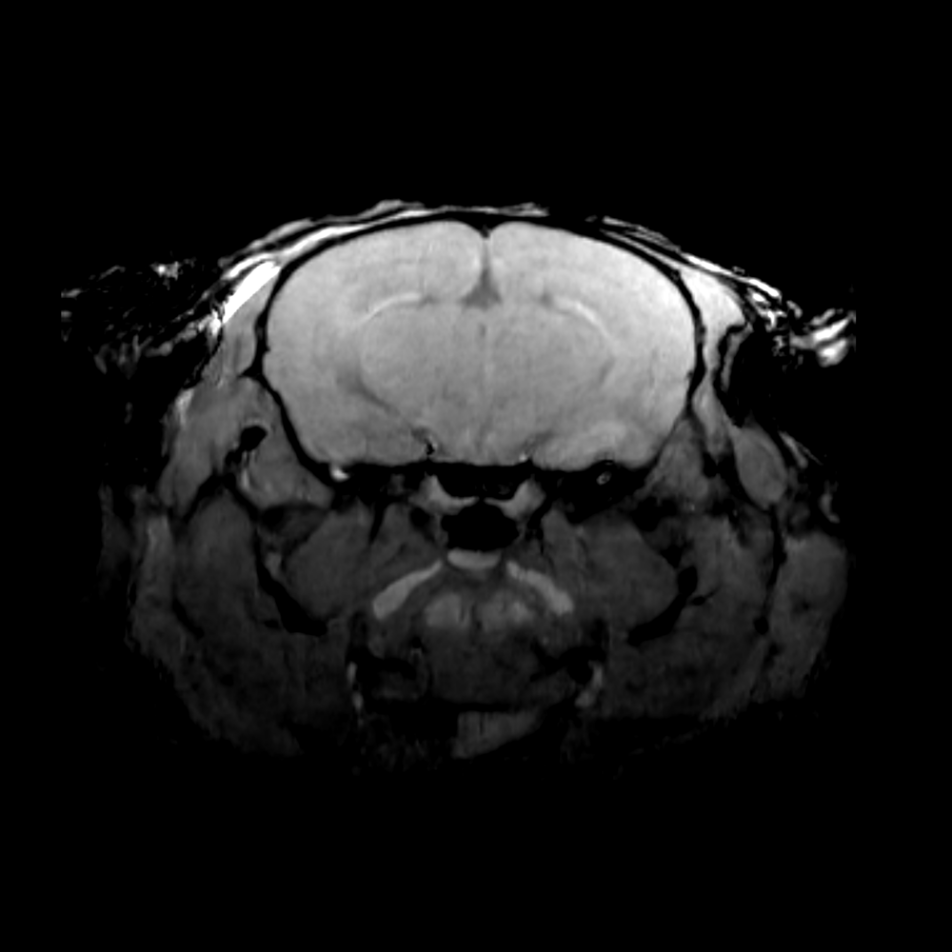

1. 神经系统精准成像:通过3D T1/T2加权成像实现脑肿瘤边界界定,扩散张量成像(DTI)追踪白质纤维束,辅助神经外科手术规划;功能磁共振(fMRI)绘制脑功能网络图谱,推动阿尔茨海默病、癫痫等疾病的机制研究。

作为临床前多模态影像技术的先锋,Mediso在磁共振MRI及其多模态融合领域取得了显著成果。通过整合结构与功能的互补数据,并结合前沿的人工智能技术,Mediso致力于实现疾病的精准诊断与智能分析,助力临床前研究向高效和精准化发展。